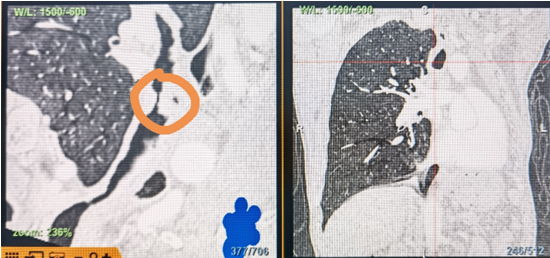

時(shí)間就是生命!了解患者病情后,歐陽(yáng)海峰立刻啟動(dòng)氣道梗阻緊急救治通道,協(xié)調(diào)院前轉(zhuǎn)運(yùn),急診快速入院流程。凌晨患者入院胸部CT顯示,現(xiàn)存唯一的呼吸通道在右主支氣管處,狹窄處僅約3毫米,患者命懸一線(xiàn)!

運(yùn)用呼吸介入技術(shù),軟硬鏡結(jié)合快速開(kāi)通氣道,是患者目前唯一可行的治療方案,手術(shù)刻不容緩!但存在麻醉后氣道完全塌陷閉合、大出血、窒息等巨大風(fēng)險(xiǎn)?;颊叽饲敖舆B轉(zhuǎn)診3家醫(yī)院,均建議保守支持治療或轉(zhuǎn)院。歐陽(yáng)海峰詳細(xì)了解患者病史,全面評(píng)估影像檢查結(jié)果后,決定盡快進(jìn)行手術(shù),組織醫(yī)護(hù)團(tuán)隊(duì)對(duì)患者進(jìn)行持續(xù)密切監(jiān)測(cè),充分保障其術(shù)前安全。